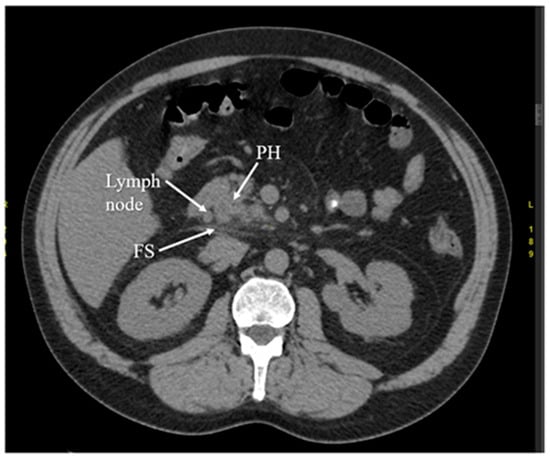

3.5. Computed Tomography

- Raghuwanshi, S.; Gupta, R.; Vyas, M.M.; Sharma, R. CT evaluation of acute pancreatitis and its prognostic correlation with CT severity index. J. Clin. Diagn. Res. 2016, 10, TC06. [Google Scholar] [CrossRef]

- Balthazar, E.J. Acute pancreatitis: Assessment of severity with clinical and CT evaluation. Radiology 2002, 223, 603–613. [Google Scholar] [CrossRef]

- Balthazar, E.J.; Robinson, D.L.; Megibow, A.J.; Ranson, J.H.C. Acute pancreatitis: Value of CT in establishing prognosis. Radiology 1990, 174, 331–336. [Google Scholar] [CrossRef]

- Mortelé, K.J.; Mergo, P.J.; Taylor, H.M.; Wiesner, W.; Cantisani, V.; Ernst, M.D.; Kalantari, B.N.; Ros, P.R. Peripancreatic vascular abnormalities complicating acute pancreatitis: Contrast-enhanced helical CT findings. Eur. J. Radiol. 2004, 52, 67–72. [Google Scholar] [CrossRef]

- Bollen, T.L.; Singh, V.K.; Maurer, R.; Repas, K.; van Es, H.W.; Banks, P.A.; Mortele, K.J. Comparative evaluation of the modified CT severity index and CT severity index in assessing severity of acute pancreatitis. Am. J. Roentgenol. 2011, 197, 386–392. [Google Scholar] [CrossRef]

- Banday, I.A.; Gattoo, I.; Khan, A.M.; Javeed, J.; Gupta, G.; Latief, M. Modified computed tomography severity index for evaluation of acute pancreatitis and its correlation with clinical outcome: A tertiary care hospital based observational study. J. Clin. Diagn. Res. 2015, 9, TC01. [Google Scholar] [CrossRef]